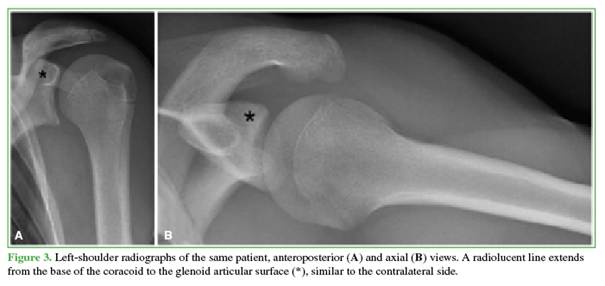

In this case, comparison radiographs of the contralateral shoulder (Figure 3) and MRI (Figure 4) were obtained to confirm the diagnosis and identify associated injuries. Given favorable clinical progress within the first 48 hours and the absence on MRI of findings suggestive of fracture or injury to the epiphyseal growth plate at the base of the coracoid, conservative treatment was indicated: analgesics for 3 days followed by a progressive return to sports over 21 days. The patient progressed well and returned to sports without restrictions.

The scapular secondary ossification centers include two main components (Figure 5): 1) Coracoid secondary ossification center: the first scapular secondary center to appear; it contributes to the upper third of the glenoid articular surface. It typically appears between 9 and 12 years and fuses with the scapular body between 12 and 16 years; 2) Inferior glenoid secondary ossification centers: multiple centers arranged in a horseshoe configuration that form the lower two-thirds of the glenoid. These usually appear between 11 and 14 years and fuse between 12 and 16 years.5 Comparison radiographs of the contralateral shoulder are an important tool, allowing reliable distinction between a pathologic fracture line and a normal physis.6,7 On CT, ossification centers appear on all planes as linear foci of bone and should not be confused with fracture lines, as occurred here. Similar diagnostic confusion has been reported—e.g., Galán-Olleros et al.8 described a comparable case in a 13-year-old basketball player—highlighting how common and relevant this pitfall is in pediatrics.